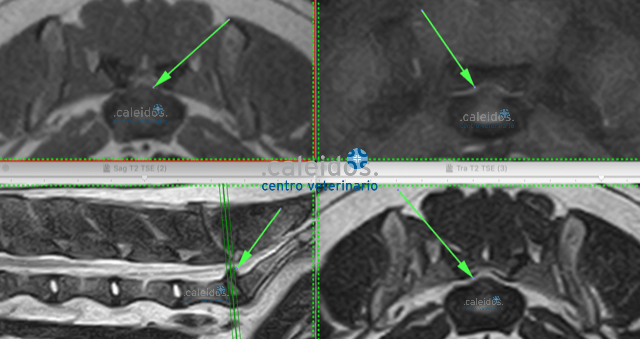

Getting to the bottom of the root of your pet's illness is our goal at Caleidos clinic, so it's essential to use every tool that can allow us to achieve it. Among these are MRI. This investigation, due to its scarce availability in the area and in particular in the veterinary field, although particularly suitable for the study of soft tissue and minimally invasive (it requires only mild sedation and does not emit harmful radiation for the animal), was, for years, performed only after resorting to other more widespread and easier techniques. Today, MRI is known as the diagnostic method of choice for brain, medullary, ligament, cartilage and some cardiovascular diseases, ones that can be promptly identified in our facility thanks to a cutting-edge, highly performing MRI equipment and to specialist staff.

At Caleidos clinic we also do MRI of knee joints, a method that is not very widespread in the veterinary field.